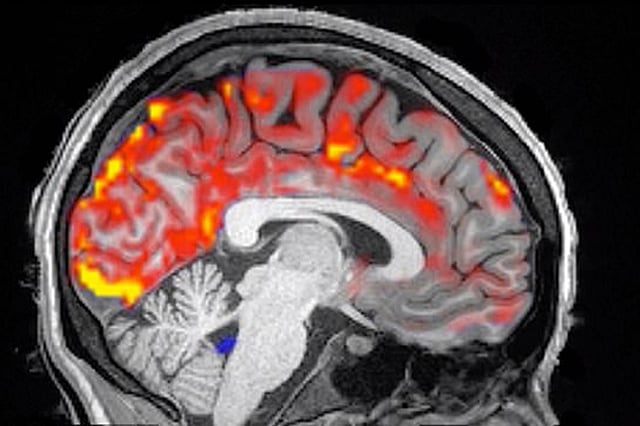

توصَّلت دراسة حديثة أجرها علماء بجامعة بوسطن الأمريكية، إلى أنَّ النوم الجيد ليلًا يقِي من الخرف، ويضمن تجنُّب التدهور المعرفي؛ وذلك بغسل الجسم من البروتينات السامة التي تؤثر سلبًا على الدماغ.

ودرس الفريق البحثي القائم على الدراسة، الحالة الصحية لـ 13 شابًا بتتبع الوضع الفسيولوجي لأدمغتهم أثناء النوم، وتبيَّن أنَّ السائل النخاعي الموجود في العمود الفقري يندفع إلى المخ كل 20 ثانية؛ بطريقةٍ تؤدِّي إلى تخليص الجسم من المواد السامة، مما يضمن للأشخاص الذين يحصلون على ساعات نوم كافية، حماية أنفسهم من التدهور المعرفي. وفقًا لصحيفة «ديلي ميل» البريطانية.

وقال الباحث المشارك في الدراسة البروفيسور لورا لويس: «إنَّ للنوم تأثيرًا كبيرًا على الدماغ أظهره تتبع حالة الدماغ أثناء النوم، وأوضحت الإشارات الكهربية المعروفة باسم (موجات دلتا) تدفق الدم بطريقة أكدت حماية الدماغ من أخطار السموم».

وأكَّد البحث الذي نُشِر في مجلة ساينس العلمية، أنَّ كتل البروتين الموجودة في المخ، تلعب دورًا في حدوث أسباب الخرف، حيث تشير الأبحاث السابقة إلى أنَّ تدفق السائل النخاعي ونشاط الموجات البطيئة يساعدان في التخلص من البروتينات السامة التي تضعف الذاكرة.